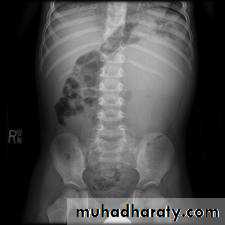

WILM’S Tumor

Most common abdominal malignancy in childhood( 1 – 5 years ) , 3% bilateral

KUB & IVU:-

Large soft tissue mass displacing bowel loops , distracted calyces ,Non functioning kidney